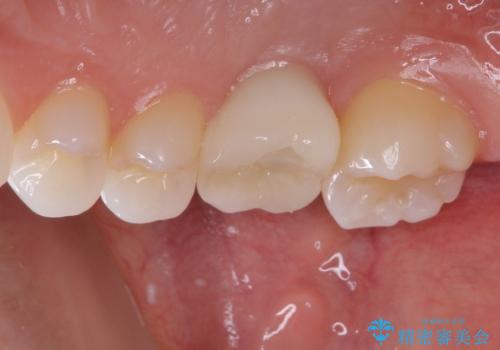

その後は、オールセラミッククラウンにて補綴することとしました。

虫歯を放置した期間が長かったため、対合の下顎大臼歯が上顎に迫ってきており、咬み合わせは非常にシビアでした。

仮歯装着中に頻繁に脱離したため、オールセラミッククラウンは脱離の少ないスクリュータイプとしました。